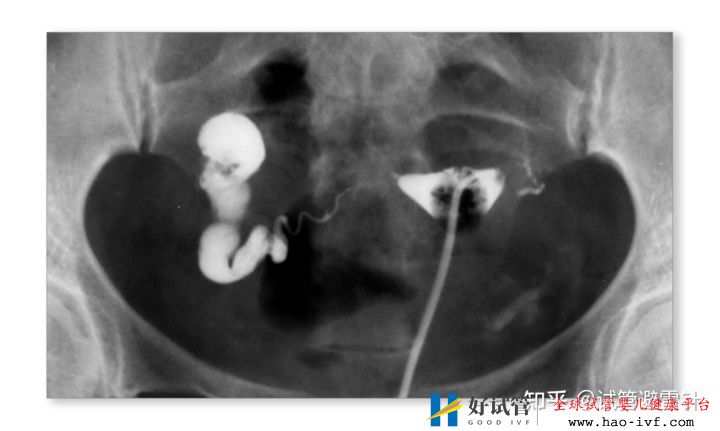

2.严重的输卵管疾病,如盆腔炎引起的输卵管堵塞和积水;或输卵管结核,子宫内膜却正常的患者;或异位妊娠手术后的输卵管堵塞。

1.女性各种因素造成的配子运输障碍

如输卵管缺如、双侧输卵管阻塞、严重盆腔粘连或输卵管手术史等输卵管功能丧失;单侧输卵管通畅,如复发性出现对侧卵巢排卵、卵巢储备功能下降者等,应适度放宽“试管婴儿指征”。